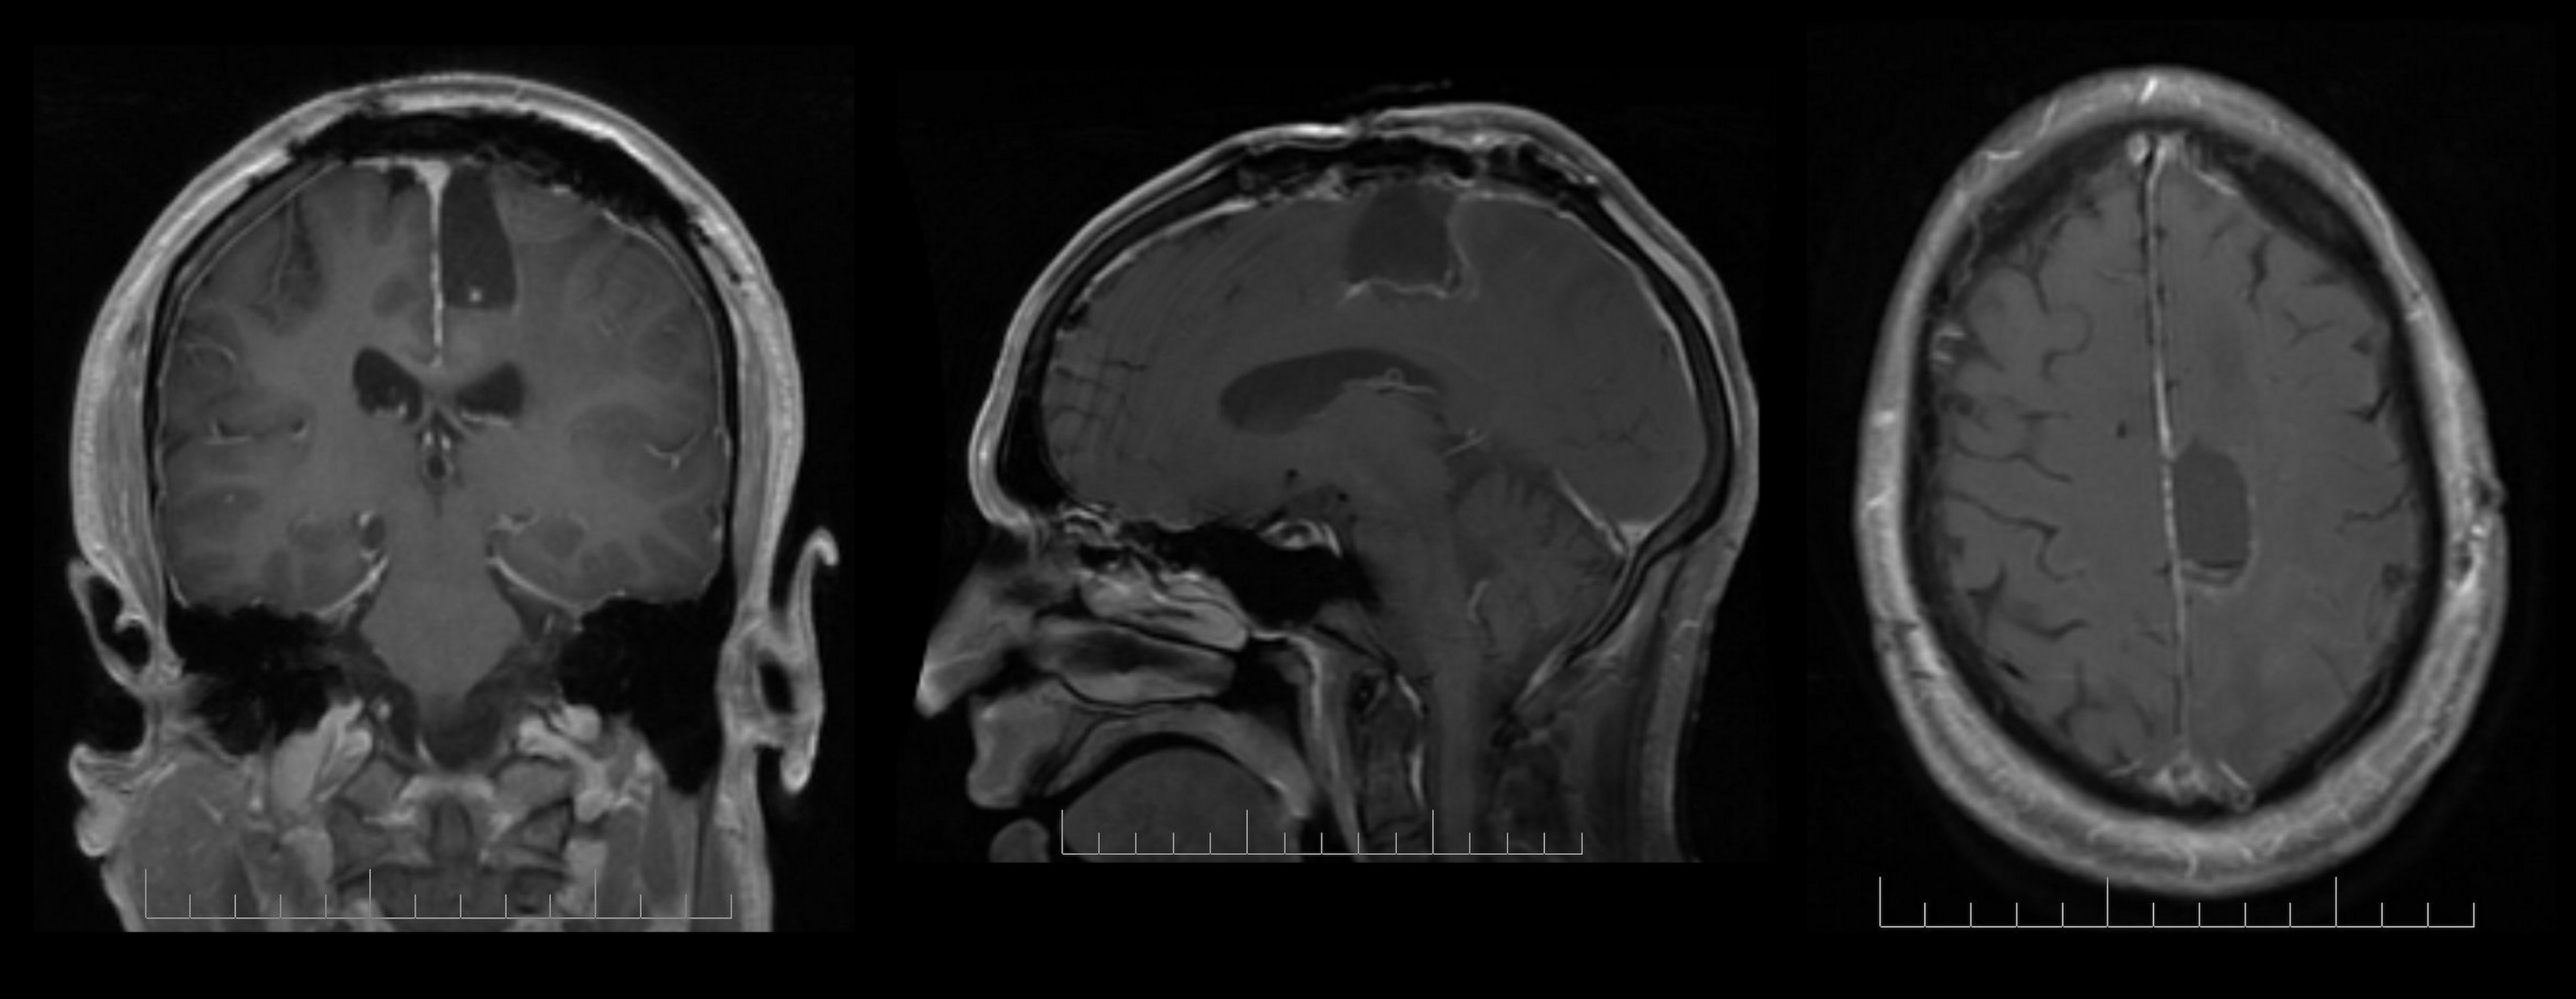

Although consistently associated with changes in grey matter, no prospective data have so far distinguished the differential effects of antipsychotic medication from psychosis progression in FEP. Sidhant Chopra, Monash University, Australia, presented the findings of a triple-blinded, placebo-controlled trial prospectively investigating changes in grey matter in medicated and non-medicated individuals following FEP.

Recruits aged 15-24 years of age received intensive psychosocial therapy and were given either an atypical antipsychotic or placebo for 6 months. Of the total 90 recruits, 62 (32 placebo; 30 active therapy) underwent neuroimaging at baseline, 3-months and 12-months as did a group of 27 healthy controls.

Over 12 months, low-dose atypical antipsychotic medication appeared to offer protective effects on the illness-related grey-matter decline seen within the hippocampus and supramarginal gyrus. Volumetric changes seen in the frontal pole, medial temporal, lateral occipital cortex and cerebellum were related to disease pathology, and appeared unaffected by low-dose medication. Greater volumetric increase within the supramarginal gyrus was associated with better symptomatic outcome, suggesting a key role for this region in mediating psychosis specific-symptomatic recovery.